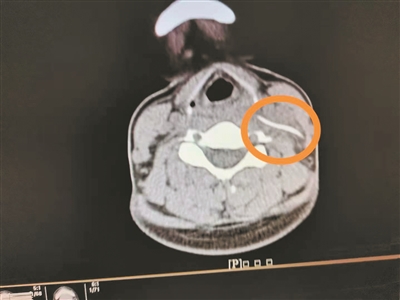

影像檢查顯示頸部異物。

4月1日,陳女士帶女兒到南方醫(yī)科大學(xué)第三附屬醫(yī)院就診,想起自己頸部不舒服,就順便到耳鼻咽喉科就診,副主任醫(yī)師曹慶碩接診后,請患者平躺檢查,此時陳女士感覺頸部更痛了,醫(yī)生懷疑頸部有異物,于是進(jìn)行了頸部CT平掃,果然發(fā)現(xiàn)左側(cè)頸動脈鞘區(qū)有異物。

明確診斷后,醫(yī)生為陳女士安排4月2日手術(shù),行“頸部側(cè)切開異物取出術(shù)”,術(shù)中見一魚刺橫行于甲狀軟骨平面的咽旁間隙內(nèi),緊貼頸內(nèi)靜脈、頸總動脈后方,周圍炎性組織包裹,幸好頸部血管無損傷,分離包裹的炎性組織,取出異物,長3.3cm。